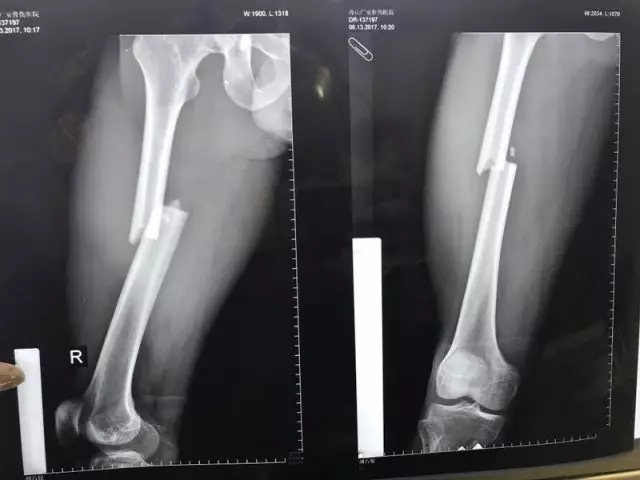

患者入院后進行了一系列檢查,發(fā)現(xiàn)股骨干處的粉碎性骨折塊移位特別明顯,下肢出現(xiàn)了短縮、外展畸形,大腿非常腫脹,內(nèi)出血很多,患者十分痛苦。

▲骨折的完美復(fù)位和內(nèi)固定